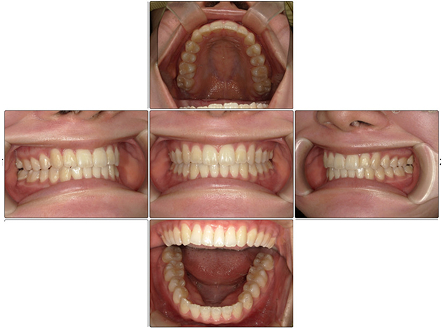

切端咬合・下顎叢生【20代・女性】

お口の中全体の写真

Before

After

- 患者の症状

- 上の出っ歯は矯正治療前よりもひっこみ、前歯が全体的に整って綺麗な歯並びとなりました。